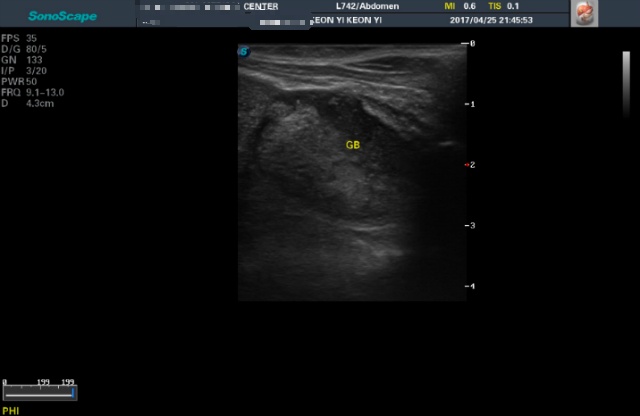

<4월25일 초진>

어제받은 초음파사진들은 몇장 안되니 그냥 다 올려볼게요

(이제와서 뭐가 뭔지도 몰라보는 이 모지란 반려인간..ㅜ)